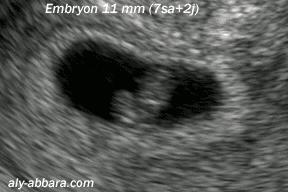

例如家兔有简单的摸胎法。

而母猪、母牛等则可以通过超声波检查等方法诊断妊娠情况。